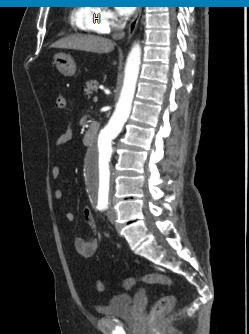

Мультиспиральная компьютерная томография является лучевым методом исследования и в режиме ангиографии применяется для диагностики сосудистой патологии брюшной аорты и ее ветвей. Сканирование проводится с помощью рентгеновских лучей, которые испускает трубка томографа, непрерывно вращаясь вокруг объекта исследования.

Особенностью КТ-ангиографии является обязательное применение контрастного усиления, которое позволяет визуализировать кровеносные сосуды. С помощью внутривенного введения йодсодержащих контрастных препаратов на снимках хорошо контрастируются висцеральные ветви и сама аорта, участки сужения и расширения сосудов, можно диагностировать атеросклеротические бляшки и тромбы в просвете сосудов.

При помощи цифровых приложений данные, полученные при сканировании, трансформируются в трехмерные изображения сосудистой системы. Это позволяет оценить пространственное соотношение анатомических структур и часто применяется в ходе предоперационной подготовки и для оценки успешности проведенной операции.